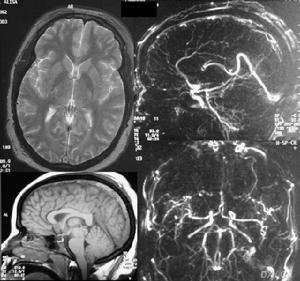

2、腦電圖、頭部CT和MRI檢查多為正常,慢性期CT無及MRI可顯示腦部多灶性及腦室周圍病變。